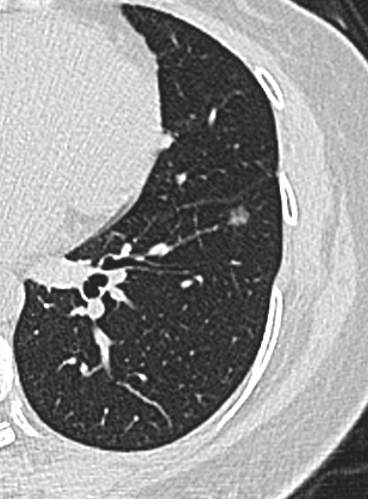

中年女性,既往体健。

21年底左下肺,直径5.2mm:

23年初复查CT左下肺GGO有所增大,直径:6.9mm